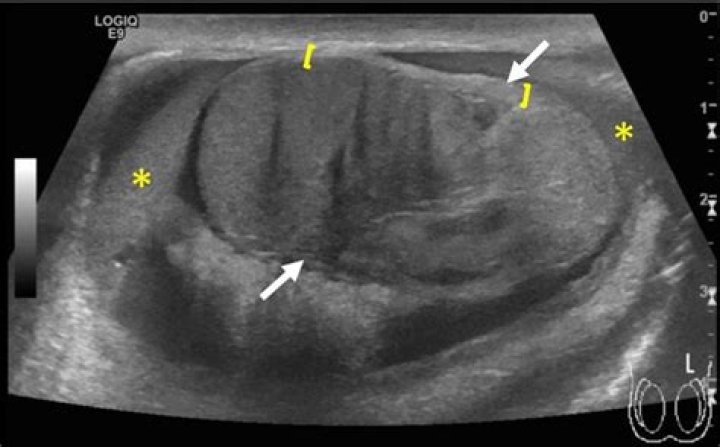

Can a testicle split in half?

Testicular rupture is a rip or tear in the tunica albuginea resulting in extrusion of the testicular contents, including the seminiferous tubules. It is a rare complication of testicular trauma, and can result from blunt or penetrating trauma, though blunt trauma is more likely to cause rupture.